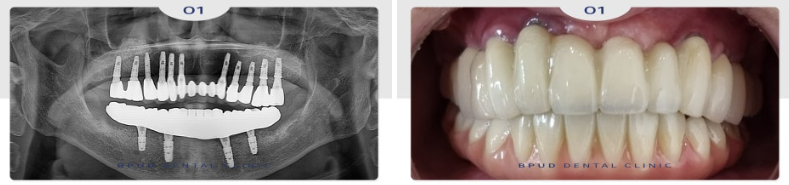

고정성 하이브리드 틀니인 매직 4로

진행하시기로 하였는데요.

신경관 앞쪽으로 4개의 임플란트를 식립하여

기존의 틀니와는 다르며 훨씬 심미적이고

단단한 지르코니아 틀니입니다.

2024.12.02

중간 과정에서는 불편함이 없도록

임시 틀니를 사용하실 수 있도록 하였습니다.

2024.12.10

이어 3개월 후, 최종 보철을 위한

모델 디자인 작업 이미지입니다.

진행 과정은 구강 스캐너를 통해

개개인의 잇몸뼈 상태, 위아래 턱의

수평적 관계 등을 명확하게 파악한 뒤,

치료 계획을 수립합니다.

이후 임플란트를 심고 임시 보철을 장착하며

마지막으로 최종 보철물이 완성되어 장착하면

치료가 마무리됩니다.

2025.01.07

최종 보철물까지 완료한 모습입니다.